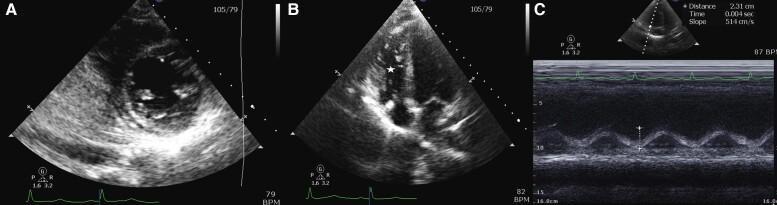

A 25-year-old female presented to the hospital with two weeks of progressive fatigue, dyspnoea, myalgias, and arthralgias. She was admitted for symptomatic anaemia requiring transfusion. Her symptoms persisted and she developed severe PH and RHF, complicated by cardiogenic shock and multiple episodes of cardiac arrest. She was found to have severe vitamin C deficiency secondary to a severely self-restricted diet. After repletion of vitamin C, the patient had complete resolution of RHF and PH.

一名25岁女性因进行性疲劳、呼吸困难、肌痛和关节痛两周前来就诊。她因症状性贫血需要输血而入院。她的症状持续存在,并发展为严重的肺动脉高压和右心衰竭,并发心源性休克和多次心脏骤停。发现她因严重的自我限制饮食继发严重维生素C缺乏。补充维生素C后,患者的右心衰竭和肺动脉高压完全缓解。